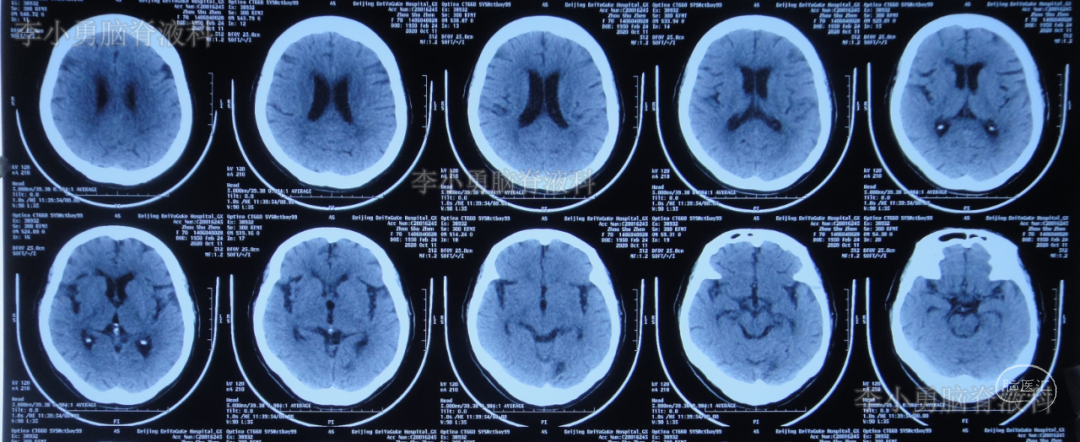

于2020年9月3日(入脑脊液科第3天,即颈椎脑脊液漏修补术后第7天即第二次颈椎病术后第25天)行脑室外引流术。术后复查头颅CT:引流管位置良好(图-11)。

图-11:2020年9月3日头颅CT

2020年10月11日(入脑脊液科第41天,拔除脑室引流管后第14天,即第二次颈椎病术后第59天)颈部伤口愈合良好,复查头颅CT:未见异常(图-17),于是转回中医骨伤科继续康复锻炼及治疗。

图-17:2020年10月11日头颅CT